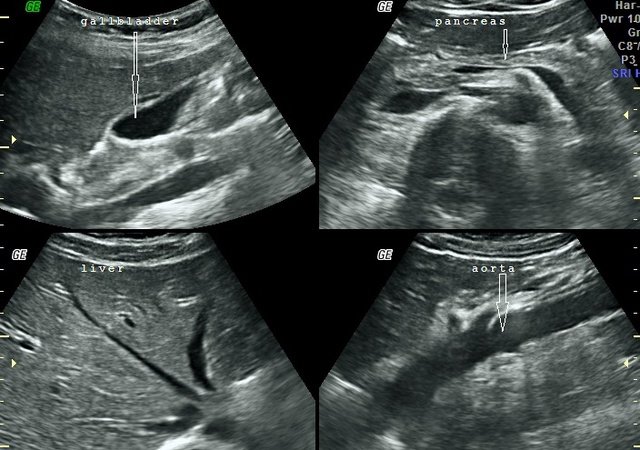

Abdominal ultrasound scans are provided for patients who experience pain above the navel and in the stomach area. The scan is performed to examine organs in the abdomen, including the liver, gallbladder, pancreas, aorta, spleen, and kidneys. The procedure detects gallstones, cysts, and tumours, alongside other pathologies.

The Abdominal Aorta scan will also be performed to measure the diameter. This would exclude any aneurysm.